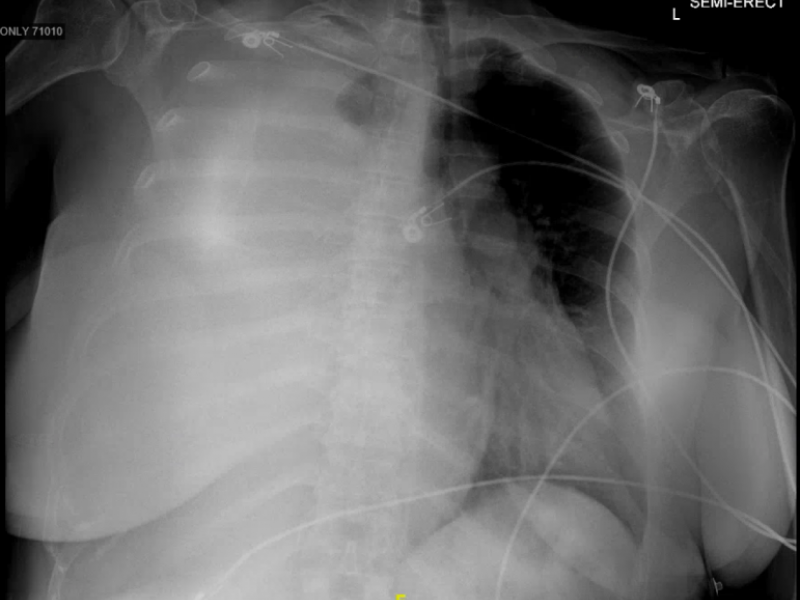

Interesting case of pleural effusion

HPI: 47 y/o F, no PMHx, sent in from UC for R sided pleural